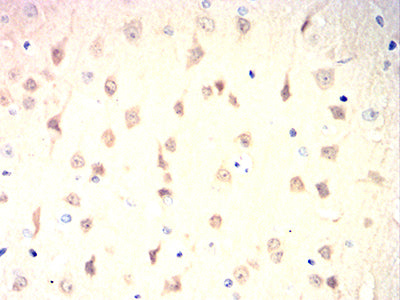

Immunohistochemical analysis of paraffin-embedded rat brain tissues using UCHL1 mouse mAb with DAB staining.